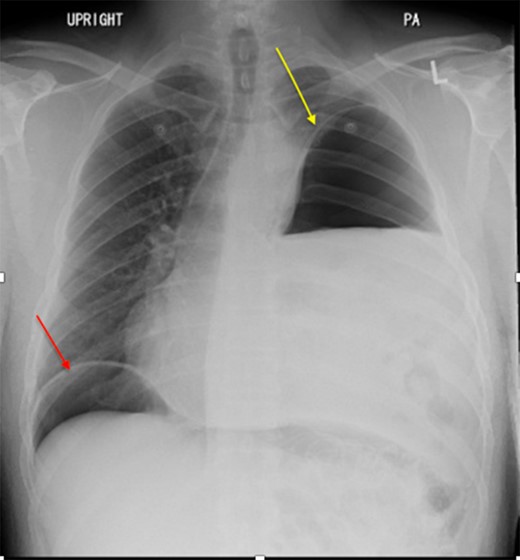

Two days later, the patient re-presented to the emergency department with left-sided pleuritic chest pain. The heart rate was 92 beats/min and the respiratory rate was 23 breaths/min on room air. The patient was stable, looked well, and his pain resolved almost entirely at time of examination. Clinically relevant labs showed a WBC of 8 × 109/L (normal range: 4–11 × 109/L). The CT did not show any significant enlargement of pneumoperitoneum; however, significant rightward shift of the mediastinum was noted. So we suggested worsening tension in the left hemithorax with further collapse of the left lung (Fig. 3). Despite being clinically stable, the mediastinal shift which was not present on the previous admission was concerning and thus the patient was taken to the operating room with the decision to repair the hernia. A left thoracotomy was used to enter the chest cavity. There was severe atelectasis of upper and lower lobes. We immediately noted a large hernia sac which encompassed the entire chest cavity and the remaining diaphragmatic muscle was significantly thinned out. The hernia sac was opened in order to identify the source of the pneumoperitoneum seen on imaging which we had suspected to be of gastric origin. Upon examination of the abdominal contents which required meticulous dissection off the herniated diaphragm from chronic adhesions, we were able to identify a well-developed perforated gastric ulcer on the anterior surface of the greater curvature of the stomach (Fig. 4). This ulcer was resected with a wedge GIA stapler and the hernia was subsequently closed by bringing the muscles together and imbricating the closure with the redundant sac using prolene sutures. Upon closure, we did not place a mesh due to the possible contamination from the gastric perforation. When the repair was complete and the patient taken off the one-lung ventilation, his lungs immediately pinked up and re-expanded. Overall, the patient tolerated the procedure very well without any post-operative complication. Two days later, we carried out an upper GI series which showed no evidence of any extravasation and his diet was advanced. On the sixth post-operative day, the patient was discharged home. He was re-evaluated in clinic 2 weeks later and continued to progress well with a stable repeat chest x-ray (Fig. 5).